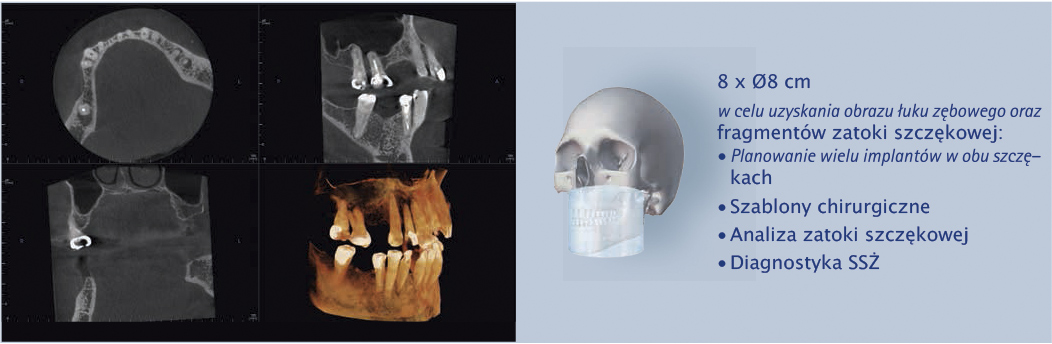

Cztery różne pola obrazowania zapewniają niezawodną diagnostykę 3D w całym obszarze jamy ustnej. Zapewniają one precyzyjne dopasowanie, odpowiednie do wskazań a także uniwersalne możliwości zastosowania w codziennej praktyce – od endodoncji, poprzez implantologię do chirurgii jamy ustnej.